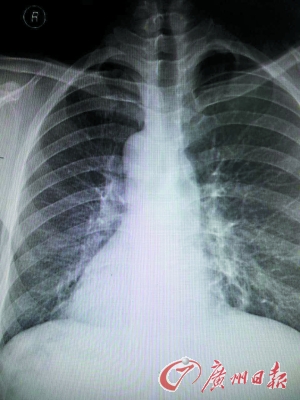

医生赶快拿起听诊器听诊心音区,发现患者右侧心音较左侧明显,跟常人相反。经胸片、心电图及B超等检查后,确诊患者为急性化脓性阑尾炎内脏反位,也就是“镜面人”得了阑尾炎。